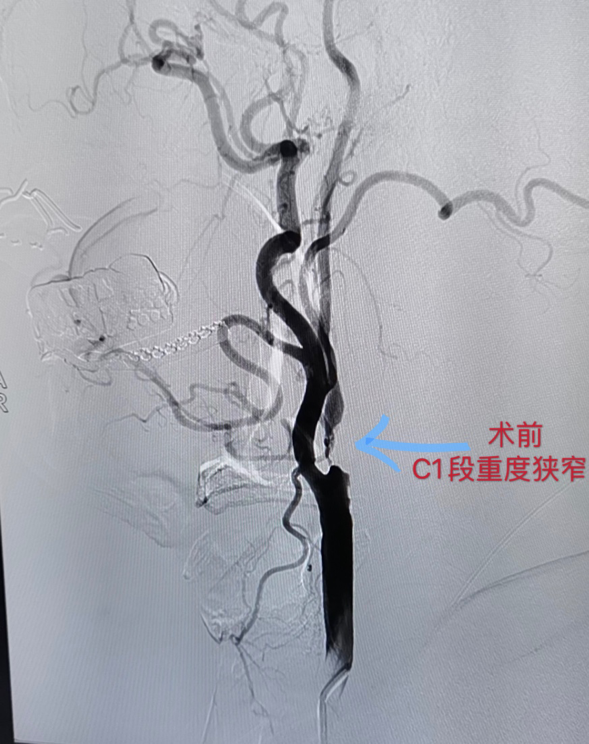

新技術(shù)——菏澤醫(yī)專附屬醫(yī)院首次成功開展頸內(nèi)動脈支架成形術(shù)

2020年9月25日,菏澤醫(yī)專附屬醫(yī)院神經(jīng)內(nèi)科、介入中心成功為一名重度頸內(nèi)動脈狹窄患者實施了頸內(nèi)動脈支架植入術(shù),標(biāo)志著我院在腦血管介入治療方面邁上一個新高度。

患者男性,73歲,頭暈伴四肢無力2年,在我院公共衛(wèi)生科宣傳下,慕名前來我院治療,9月17日入住神經(jīng)內(nèi)科。根據(jù)病史、臨床表現(xiàn)、頸動脈超聲等影像學(xué)檢查后,發(fā)現(xiàn)該患者右側(cè)頸動脈粥樣硬化伴斑塊形成,右側(cè)頸內(nèi)動脈重度狹窄,診斷為短暫性腦缺血發(fā)作(頻發(fā))、腦梗塞、多發(fā)腦血管狹窄。由于病情復(fù)雜,情況嚴(yán)重,神經(jīng)內(nèi)科立即組織病例討論,最終決定對患者實施介入手術(shù)治療。在完善各項術(shù)前檢查及準(zhǔn)備工作,排除介入診療禁忌并征得家屬同意后,于9月25日為患者在局麻下行右側(cè)頸內(nèi)動脈支架成形術(shù),術(shù)中造影顯示右頸內(nèi)動脈C1段管腔重度狹窄,狹窄度達(dá)95%。隨后針對病變血管行血管腔內(nèi)支架成形術(shù),手術(shù)順利,獲得成功。術(shù)后造影復(fù)查顯示血流通暢,狹窄解除。但術(shù)后患者心率、血壓下降,考慮頸內(nèi)動脈支架術(shù)后影響壓力感受器所致,隨即轉(zhuǎn)入ICU觀察治療,目前患者狀態(tài)良好,家屬表示很滿意。

頸動脈血管腔內(nèi)支架成形術(shù)目前是治療頸動脈狹窄的最有效方法之一,較以往的頸動脈內(nèi)膜剝脫術(shù),具有創(chuàng)傷小、并發(fā)癥少、恢復(fù)快的優(yōu)點。目前,該治療方法已經(jīng)寫入美國缺血性卒中防治指南中,這一微創(chuàng)手術(shù)對中風(fēng)的預(yù)防有著重要作用。

這是我院一次神經(jīng)內(nèi)科、介入科、ICU多學(xué)科聯(lián)合協(xié)作共同完成的一項新技術(shù),填補(bǔ)了我院神經(jīng)內(nèi)科腦血管介入治療方面的歷史空白,譜寫了新時期我院發(fā)展的新篇章!